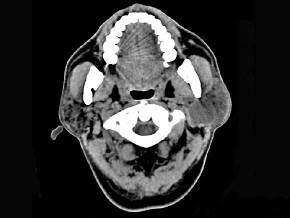

问题 男性50岁,涕中带血半年,体检发现右侧颈部多个硬结,CT扫描如图所示,请选择正确的描述和结论 ( )

选项 A、考虑为右侧筛窦黏液性囊肿 B、考虑为右侧筛窦癌 C、软组织影累及对侧筛窦、右侧上颌窦 D、右侧眶内壁、上颌窦壁及颅底骨质破坏 E、右侧筛窦内见软组织块影,边缘不规则

答案 BCDE